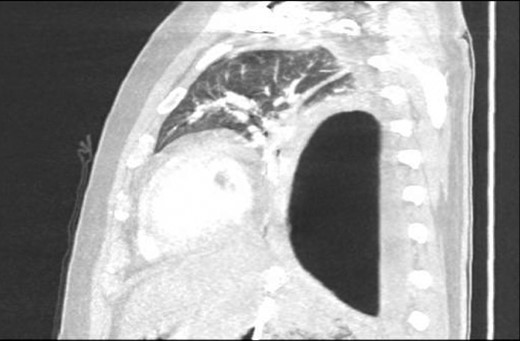

Chest X-ray in ICU following drainage showed what was thought to be Pneumomediastinum (Figs 1 and 2), and given this concern he was referred to the Cardiothoracic service. Subsequent CT suggested a large loculated hydro-pneumothorax, which in retrospect represented the drained Pseudocyst communicating through the diaphragm (Figs 3 and 4).

Area of communication between the drained Pseudocyst and the Left Pleura. Space noted with arrow.